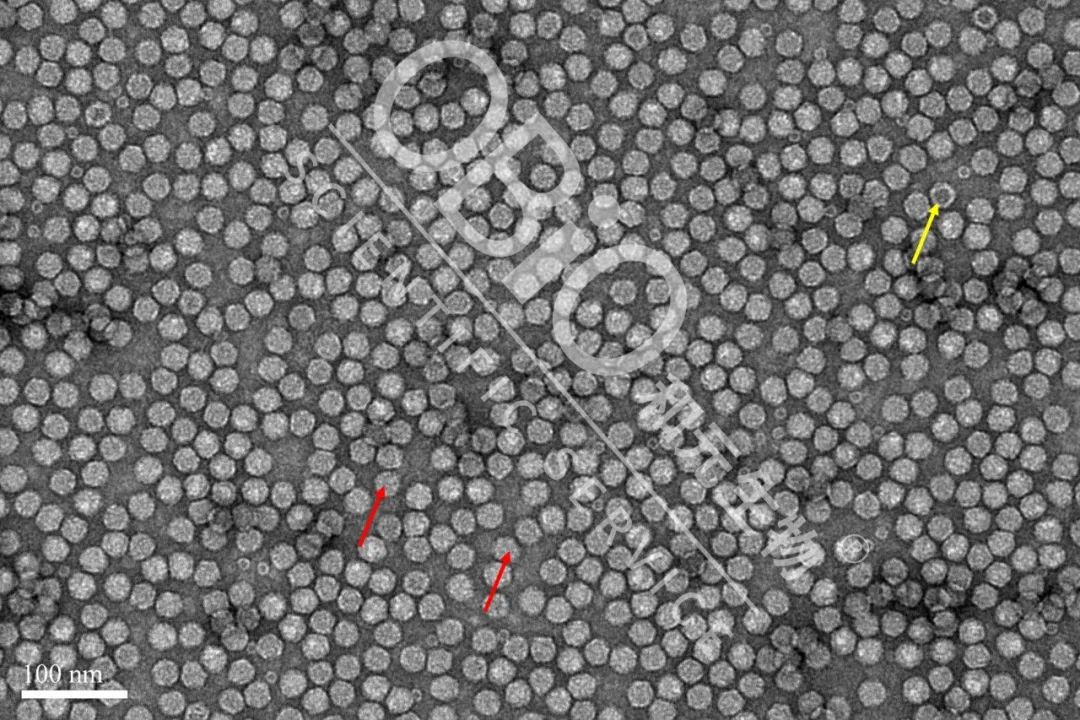

图2 至尊国际·(中国)至尊服务,至尊享受 rAAV载体生产空壳率

电镜结果:包装DNA基因组的病毒颗粒为实心颗粒(红色箭头);空病毒颗粒中间存在空洞(黄色箭头)